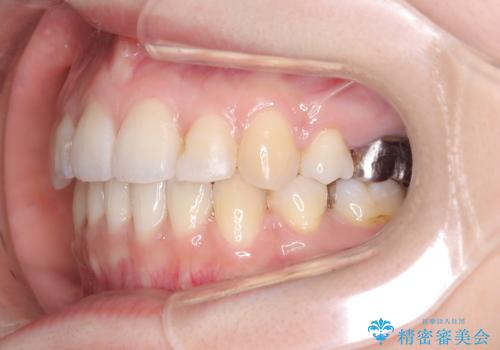

【ワイヤー矯正】口元を下げたい、下の歯の凹凸を無くしたい

- 主訴:口元を下げて前突感を無くしたい、下の歯の凹凸も無くしたい

右側第二小臼歯、左側第一小臼歯、下顎両側第一小臼歯を抜歯しワイヤ-矯正を行いました。

骨格的顎の変位を認めたため、顔貌に対しピッタリ上下の歯の正中を合わせることは難しいと説明し、上下左右計4本小臼歯を抜歯しワイヤー矯正治療を行いました。